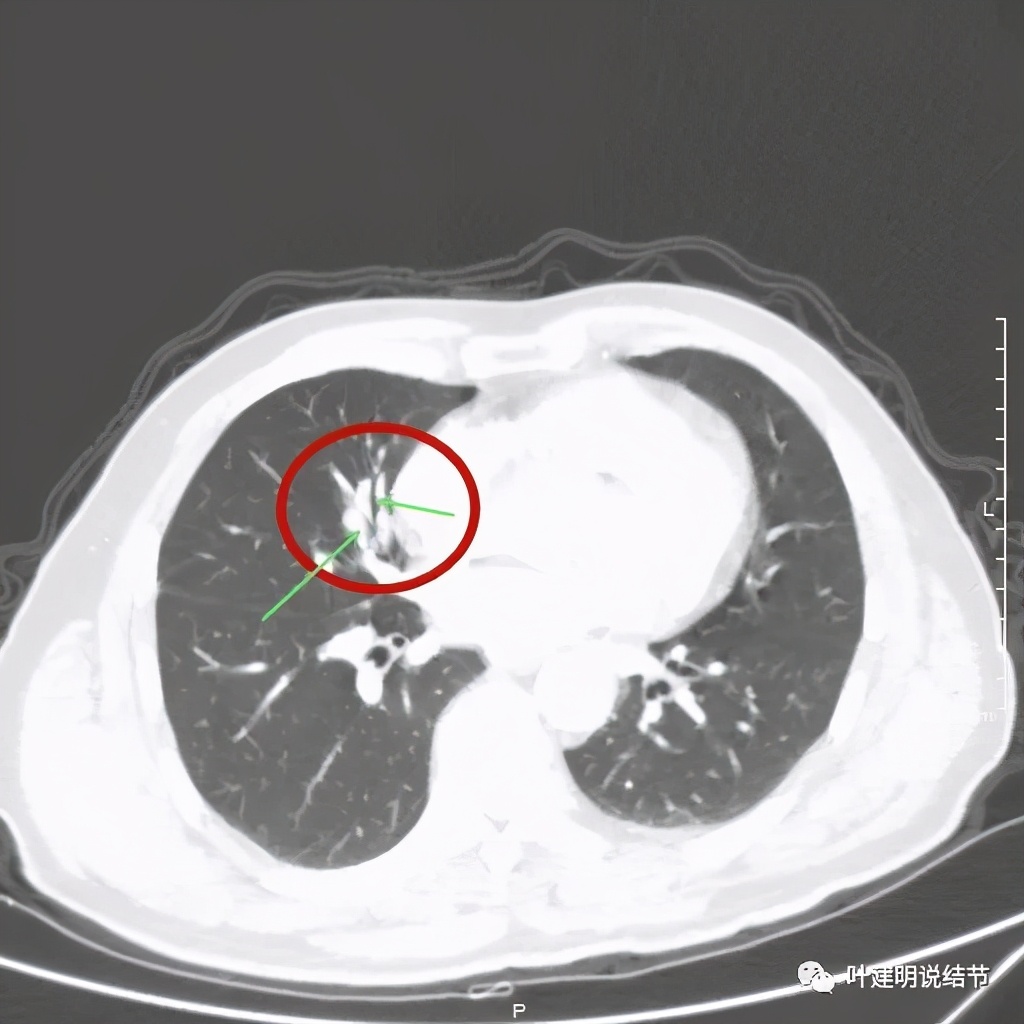

上图绿色箭头示支气管通气征